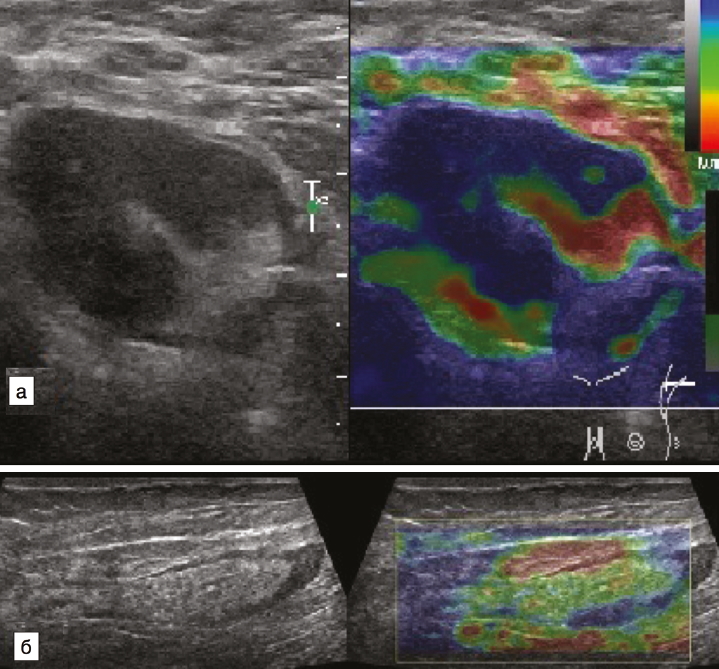

В последние годы широкое распространение получил метод ультразвуковой эластографии и эластометрии. Данная методика представляет собой способ дифференциации тканей по их жесткости путем механического воздействия на них и анализа деформаций, получаемых с помощью ультразвуковых диагностических сканеров [23]. Для оценки жесткости лимфатических узлов используется система качественной оценки результатов компрессионной эластографии лимфатических узлов, разработанная и M. Furukawa и соавт. в 2007 г. [24], согласно которой выделяют 4 степени жесткости узлов: 1-й тип (мягкие), 2-й (умеренно мягкие), 3-й (умеренно жесткие) и 4-й (жесткие). Для метастатических лимфатических узлов характерна жесткая и жестко-неоднородная структура, что соответствует 3 и 4-му типам эластографической картины по M. Furukawa, а для гиперплазированных лимфатических узлов – 1 и 2-й тип эластографической картины (рис. 5).

Рис. 5. Компрессионная эластография лимфатических узлов: а – лимфатический узел с метастатическими изменениями; отмечается неоднородная жесткая структура (3-й тип эластографической картины); б – гиперплазированный лимфатический узел (1-й тип эластографической картины).

Fig. 5. Strain elastography of lymph nodes: a – metastatic lymph node with heterogeneous hardness (elastographic pattern 3); b – hyperplastic lymph node (elastographic pattern 1).